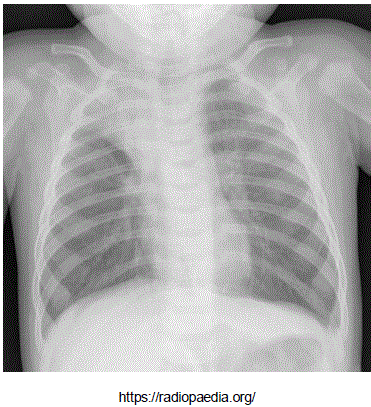

Adolescente masculino, 13 anos de idade, portador de anemia falciforme em seguimento regular com hematologista, apresenta queixa de febre e tosse há dois dias e dor em face anterior do tórax a direta. Ao exame clínico encontra-se em regular estado geral, levemente descorado, FC: 84 bpm, FR: 34 ipm, Saturação de Oxigênio: 95% em ar ambiente, Temp: 38°C, PA: 100/60 mmHg. Realizou radiografia de tórax, que mostrou a imagem abaixo:

Provas

Radiografia de tórax realizada há 15 minutos:

Com relação ao suporte hídrico prescrito, está correto afirmar que: